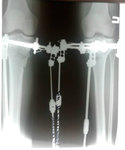

Дата операции 21.03.2018г.

Дата снятия аппаратов 06.07.2018г.

Срок лечения 105 дней.